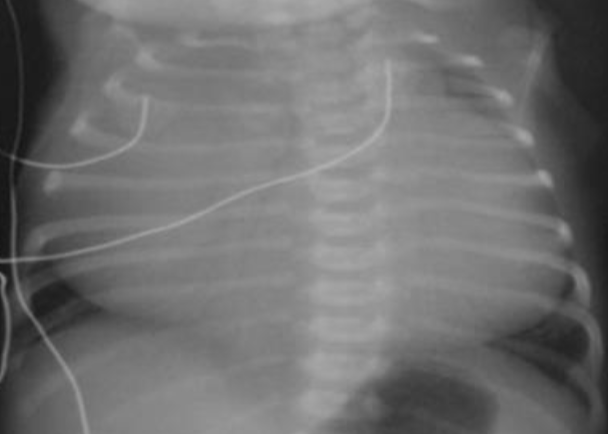

- Anterio-posterior [AP] chest radiograph shows multiple cystic lesions inâ (1 -the middle and lower zones of the left hemi-thorax with ill-defined left hemi diaphragm. There is mediastinal shift toward the right. These lesions are -bowel loops inside the left hemi-thorax. The film is over exposed (over .(penetration

- The diagnosis is Left Sided Congenital Diaphragmatic Hernia (CDH). This - (2 is called bockdalic CDH. CDH is usually in the left side (90 %). The defect is found in the posterio-lateral aspect of the diaphragm. CDH is associated with .lungs hypoplasia in the same side and to a lesser extent in the opposite side .This may be complicated by pulmonary hypertension and severe hypoxemia

- The treatment of CDH is immediate endo-tracheal incubation if it is - (3 diagnosed in-utero or if it is highly suspected after birth (with following symptoms and; respiratory distress (RD), cyanosis, asymmetrical chest movement, bowel sounds heard in the chest and scaphoid abdomen). After intubation, the patients is put on mechanical ventilator and the pulmonary hypertension [PH] is controlled and hypoxemia is reversed. PH and severe hypoxemia may require inhaled Nitric Oxide [iNO], High frequency Oscillatory Ventilation [HFOV] and Exogenous Surfactant administration through endotracheal tube [ETT]. After the stabilization of the arterial blood gases the patient is taken to suture the defect. If the defect is large, a mesh,[ABGs] device may be used. The most important differential diagnosis is Cystic .Adenomatoid Malformation [CAM]